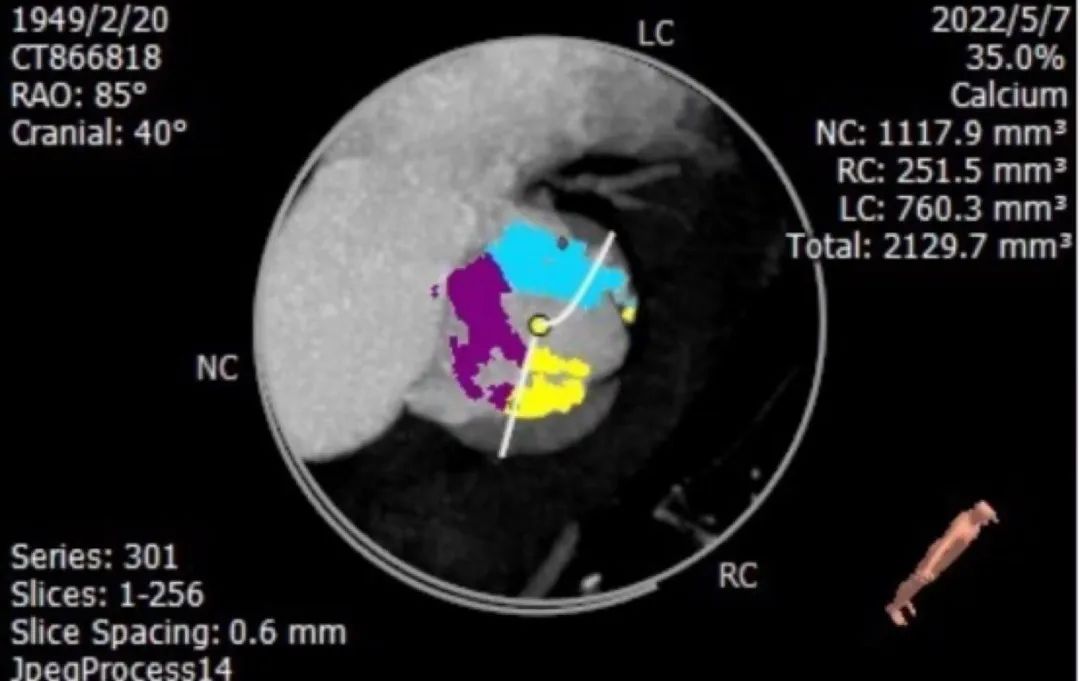

瓣叶增厚、重度钙化

图片

钙化积分2129mm²

主要在瓣叶及瓣叶交界处

1. 患者钙化非常严重,Type 0型二叶瓣,钙化积分高达2100+,钙化主要分布瓣叶、瓣叶交界,升主动脉严重扩张,必要时使用Snare辅助过弓和跨瓣;

对于Type 0型二叶瓣且钙化积分达到2100+,这种非常特殊病例,在瓣膜选择上需要非常谨慎: